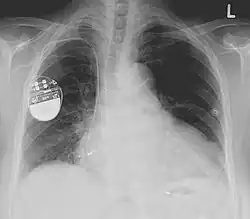

Pacemaker

Een pacemaker is een apparaat dat ervoor zorgt dat het hart in het juiste ritme blijft pompen door elektrische impulsen te genereren geleverd door elektrodes. Aanvankelijk werden pacemakers gebruikt om een te traag hartritme (bradycardie) te corrigeren. Later werden ze ook toegepast bij een te snel hartritme (tachycardie), en bij patiënten met een risico op een hartstilstand of met hartfalen. Het apparaat ter voorkoming van een hartstilstand wordt implanteerbare cardioverter-defibrillator (ICD) genoemd. Bij hartfalen wordt een biventriculaire pacemaker ingezet. Als het hart stil komt te staan of onregelmatig klopt, zal de pacemaker een elektrische prikkel geven, waardoor de normale hartslag hersteld wordt.

Pacemakers worden gevoed door 2,5 volt lithium-iodine batterijen. Een pacemaker gaat zo'n acht tot tien jaar mee, daarna moet hij worden vervangen. De apparaatjes zijn klein; ongeveer 20 cc en 20 gram zwaar. Ze kosten gemiddeld zo'n 3000 euro. Doordat ze meestal vlak onder de huid geïmplanteerd worden, is dit geen ingrijpende zaak. Men verblijft meestal één nacht na de ingreep in het ziekenhuis ter observatie. Het vervangen van de pacemaker kan in dagopname; het is een kleine ingreep.